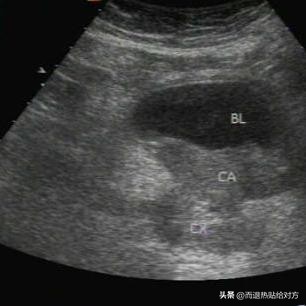

葛先生咨询医生。葛先生工作繁忙,常常需要加班和出差。他的妻子一直是个勤俭持家的好妻子,从未因此抱怨。每次加班回家,都有热乎乎的饭菜等着。出差回来,总会有整洁的衣物。这些小心照顾让葛先生感受到温馨。妻子在8年前绝经,当时情绪不稳定,经常失眠。因此,为了让她有好的睡眠,葛先生和她分房睡。然而,昨晚葛先生还没回家,就接到妻子的电话:“老公,你回来时给我带包卫生巾。”葛先生不解,明明早就绝经了,为什么需要卫生巾?“老婆,你怎么又来月经了呢?好几年都没了。”老婆笑着说:“不知怎么的,我又来了。好了,别说了,回来别忘了买啊!”葛先生觉得不对劲,认为妻子的情况不太可能是月经,可能有其他疾病。他感到紧张,决定带她去医院检查。回家后,告诉妻子这一决定。妻子却不以为然:“你多虑了,我没事。去医院浪费钱。”葛先生坚持,第二天带着妻子去医院检查。检查结果出来后,医生告知是宫颈癌,建议尽早住院治疗。但妻子不愿住院,心疼花钱,平时小病也忍耐。现在确诊为癌症,她认为没必要治疗,选择吃药,死活不去医院。葛先生心疼无奈,只能偷偷找医生咨询。“大夫,我妻子被确诊宫颈癌,只想吃药治疗,这样下去她还能活多久?”医生无奈地说:“宫颈癌对女性危害大,导致出血、排液,晚期还有恶病质,让患者消瘦、贫血。未治疗的宫颈癌患者寿命不确定,因个体差异、癌细胞扩散程度和身体状况各异。早期患者或许只能活一两年,晚期可能仅几个月。如果患宫颈癌,最好及早就医。”“但我怎么劝她都不听,是否应该去医院治疗?”葛先生感到痛苦。医生表示:“宫颈癌患者需养成良好生活习惯,保持充足休息。护理人员应密切关注患者状况,勤换勤洗*裤内**,保持*裤内**宽松。阴部清洁时,使用温和物品,避免刺激。心理上,患者承受巨大压力,需沟通和开导。”葛先生听后感激不已。他决定回家好好劝说妻子,让她接受正规治疗。【参考文献】:[1]陈晓霞, 赵晓娟, 李晓娟, 等. 宫颈癌发病机制的研究进展[J]. 中国妇幼保健, 2018, 33(15): 1971-1974。【注】:本文为同行业真实案例,与大家分享交流。